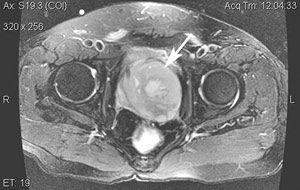

相关图片